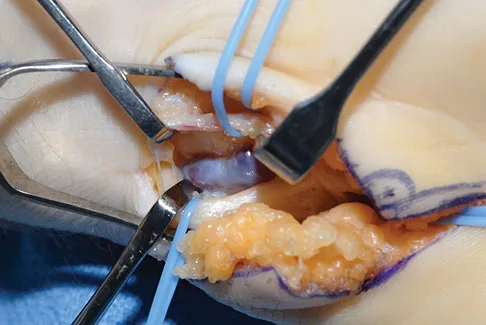

Question 39

A 25-year-old man shot himself at the base of the right index finger while cleaning his handgun. Examination reveals that the finger is cool and cyanotic. A clinical photograph and radiograph are shown in Figures 44a and 44b. What is the recommended treatment?

Explanation